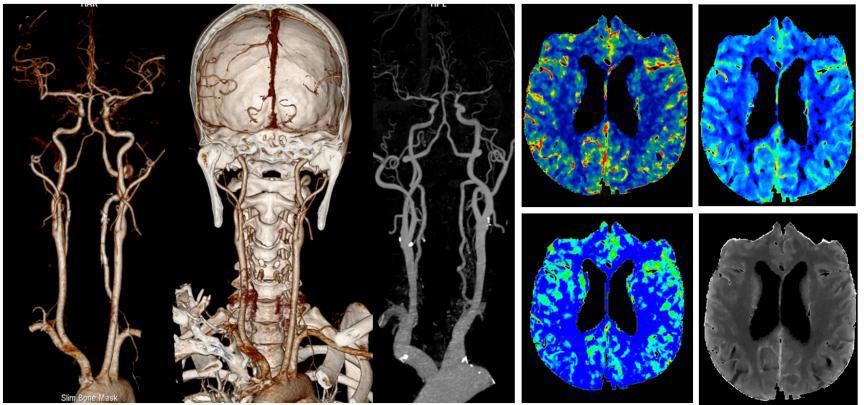

更全面:一站式全身扫描

该CT拥有16厘米宽体等焦宝石DOD探测器,是目前业内最宽探测器,百万像素超高分辨率检查+3mm超低密度分辨率,将小病灶显示得更清楚、边界更清晰。可轻松覆盖心脏、颅脑、肝脏等器官,搭配独有的自由组合一站式联合扫描技术,能够一次性实现多血管或多器官联合扫描,大幅提升胸痛三联征、冠脉多部位联合扫描、心脑血管上下肢及胸腹血管病变的检出率,为让患者得到及时科学有效的诊疗提供了强有力的技术保障。

更精准:能谱应用广

Revolution CT我们又叫256排能谱CT,能谱能做到如物质的定量分析,现临床上运用较多的是痛风石的早发现、泌尿系统及胆道系统结石成分的分析;为临床医师的治疗方案提供精准方向。